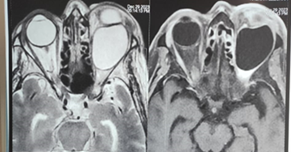

Figure 3. Orbital MRI : Extra conical

intraorbital cystic formation with thin and regular wall in hyposignal on all

sequences not enhanced after gadolinium injection measuring 35x28x27 mm, the

content is in T1 hyposignal, T2 hypersignal disappearing on the FLAIR sequence

without restriction of dissidence or enhancement after injection of gadolinium

this mass exerts a mass effect on the intraorbital structures (the eyeball, the

superior rectus muscle and the optic nerve).